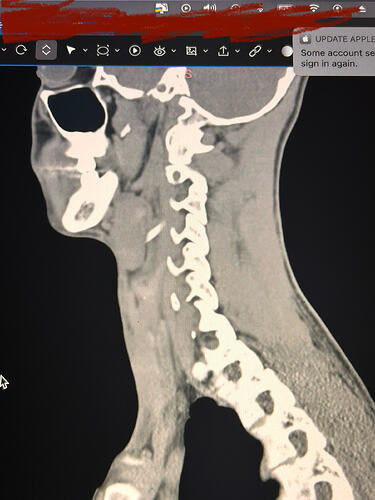

Here are some images of my 3-d ct, thanks for taking an interest it means a lot!

Oh and I almost forgot these were taken before I had my right styloidectomy

Things of note that I can see in your imaging - You’ve completely lost the natural lordotic curve in your cervical spine. That alone can bring the styloids & hyoid bone into closer proximity to nerves & vascular tissues in the neck though it has been speculated that the neck curve is lost when there’s IJV compression due to ES as the body’s way of trying to create more space for the IJV so it can drain the deoxygenated blood from the brain more efficiently. The lordotic curve can be restored w/ gentle exercises but it takes patience & is a slow process. The following link has helpful information about cervical curve restoration.

In this image of your left styloid, it appears from the angle of the picture that your left styloid is extremely close to the left transverse process of C1 (green circled area). If that’s truly the case, your left IJV is likely being squashed between the two & that means your vagus nerve is most likely being squashed at that point, too. Some of your symptoms could be vagal related. Also due to the angle of the image, it appears the greater horn of your hyoid could be very close to your spine which can cause internal/external carotid artery compression but can also cause symptoms that point to hyoid bone syndrome as you’ve suggested. Unfortunately, it doesn’t appear the CT scan was done w/ contrast as none of your veins or arteries appear in the images you posted & contrast is necessary to see those.

I could give you more precise information if your styloids, hyoid & C1 were shown in the sagittal plane (from the side) vs. from behind as they are. Below is a picture showing the anatomical planes of the human body:

I’ll just add in as well that in your first image, the hyoid bone processes look pretty thick, more than you’d expect, so could well be part of your issues, but I do agree with @Isaiah_40_31 that your left styloid is very close to the C1 process, the right side looks a little longer than average… Also looking at the 1st & last images (I’m sorry, | can’t label them for you), there’s calcification below your hyoid which I’m presuming is the thyroid cartilage, it lookd pretty chunky compared to most people’s, so this could possibly be causing some issues too?

Here are some of my 2-d scans, thanks. The top one is my right greater horn and the bottom is the left